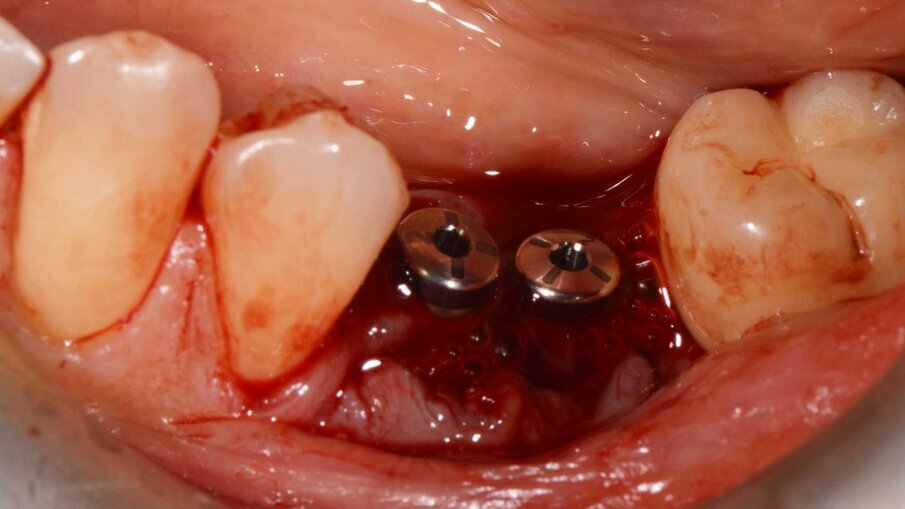

Un paziente di 47 anni, non fumatore e in buono stato di salute, all’esame clinico presenta una perimplantite diagnosticata dopo 7 anni di carico a livello degli impianti 3.5 e 3.6, con un sondaggio di 8 mm sull’aspetto mesiale dell’impianto 3.5 e di 4,5 mm sull’aspetto distale del 3.6. La radiografia conferma la perdita ossea attorno all’impianto distale e ancora più evidente a livello dell’impianto mesiale (Fig. 1). Si decide di trattare il caso chirurgicamente decontaminando la zona affetta, utilizzando il gel REGENFAST per potenziare il trofismo topico e inserendo la matrice Geistlich Fibro-Gide a sostegno dei tessuti molli coronali. Si procede con il trattamento chirurgico, esponendo il difetto per rimuovere il tessuto di granulazione (Fig. 2). La superficie implantare esposta è ulteriormente ripulita con ultrasuoni, spazzolino in titanio, passando all’interno delle spire e risciacquando con soluzione fisiologica e garze sterili (Fig. 3). Successivamente, il gel REGENFAST è dosato e posizionato direttamente all’interno del difetto perimplantare mediante spatolina o puntale (Fig. 4). La matrice Geistlich Fibro-Gide è ritagliata in modalità “Collagen-Ring” affinché possa essere posizionata attorno al collare implantare, sostenendo i tessuti molli che non collasseranno all’interno del difetto (Fig. 5). La matrice, grazie all’elevata porosità è completamente permeata di sangue permettendo la stabilizzazione del coagulo. La matrice viene ulteriormente imbevuta di gel REGENFAST così da potenziare i fisiologici processi rigenerativi (Fig. 6).

Fig. 4 - Il gel REGENFAST è dosato e posizionato direttamente all’interno del difetto perimplantare mediante spatolina o puntale.